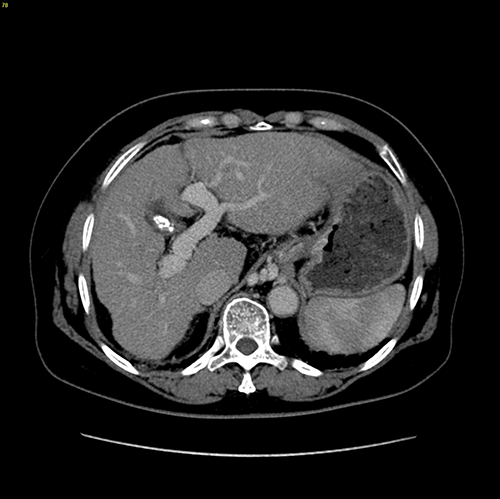

门脉高压、右肝动脉门静脉瘘、胆囊结石----脾切除、贲门周围血管离断、肝右动脉结扎、胆囊切除